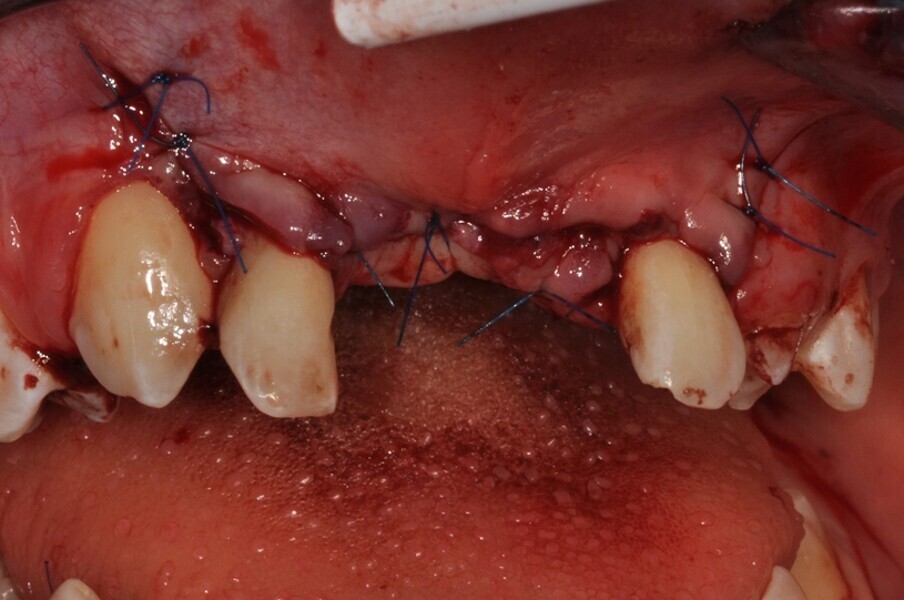

Ryc. 4¬_Stan miejscowy po ekstrakcji i ablacji kości.